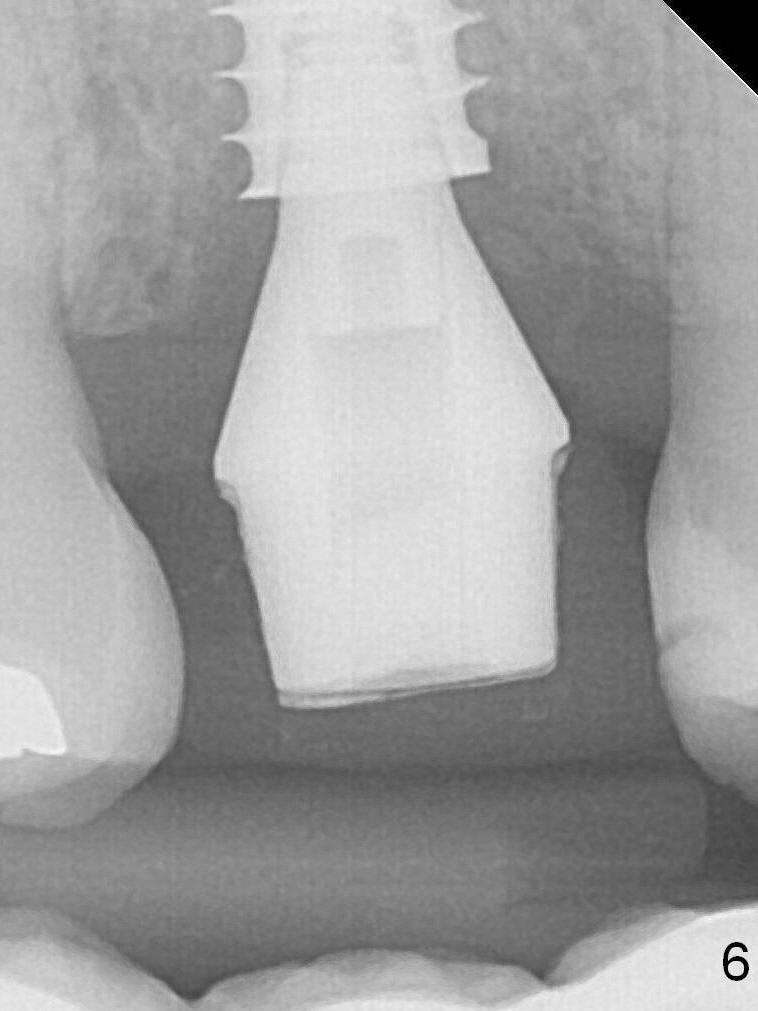

There is no bone loss 3 months postop (Fig.6,7).  The screw needs to be retightened 9 months post cementation (Fig.8).